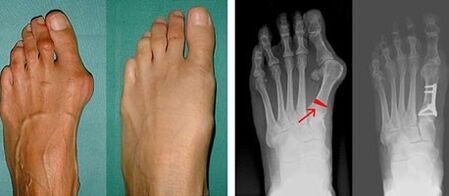

V první fázi identifikace valgusu palce a malíčku u nohy lékař provede vizuální vyšetření. Tímto způsobem určuje stupeň vývoje patologie. Aby bylo možné identifikovat podrobné změny v kloubech, jsou předepsány rentgenové snímky a plantografie.

Pokud vizuální vyšetření a rentgenové paprsky neposkytnou žádný výsledek, je pacient odeslán na plantografii, aby se určily možné ploché nohy. Tato metoda spočívá v pořízení otisků chodidel, na základě kterých se pacientovi vyrobí obuv nebo vložky s ortopedickými vlastnostmi. Poté je pacientovi předepsána podometrie. Tato metoda využívá počítačovou analýzu k určení tlaku váhy osoby na chodidla. Výsledky pokročilé diagnostiky jsou základem pro volbu léčebné metody zakřivení prvního a druhého prstu nohy.

Nevýhodou RTG vyšetření je nutnost ozařování nohou pacienta, což řada pacientů nemá ráda. Myslí si, že je to příliš škodlivá metoda. V tomto ohledu nelze bez výsledků plantografie zahájit účinnou léčbu hallux valgus.